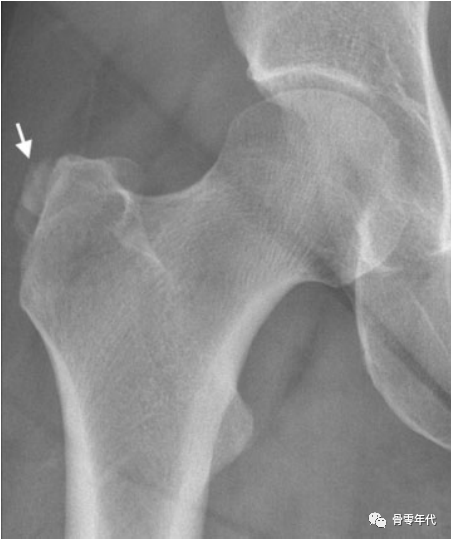

肌腱病的典型特征是肌腱在T1加权图像上信号强度增加,而在T2或质子密度加权图像上没有任何信号异常。慢性肌腱病可能与皮质异常、硬化、末端隆起和肌腱附着处的大转子小囊肿有关。

(a)一位74岁女性的右侧髋关节侧位X线片显示臀小肌腱附着处有一个大的突起(星号)。(b)重度臀小肌腱病(白色箭头),在矢状面T1加权像上插入末端(星号):仅有轻微的臀中肌腱病(黑色箭头),伴有微小的末端隆起。(c)轴位T1加权图像显示臀小肌严重脂肪变性,最明显的是后部和中部(白色箭头)。

由于炎症反应,羟基磷灰石晶体的沉积可能会引起剧烈的疼痛。在急性期,肌腱及其周围可见严重的水肿症。X线片有助于诊断钙化性肌腱炎或滑囊炎,因为钙化沉积在mr图像上很容易被忽略。